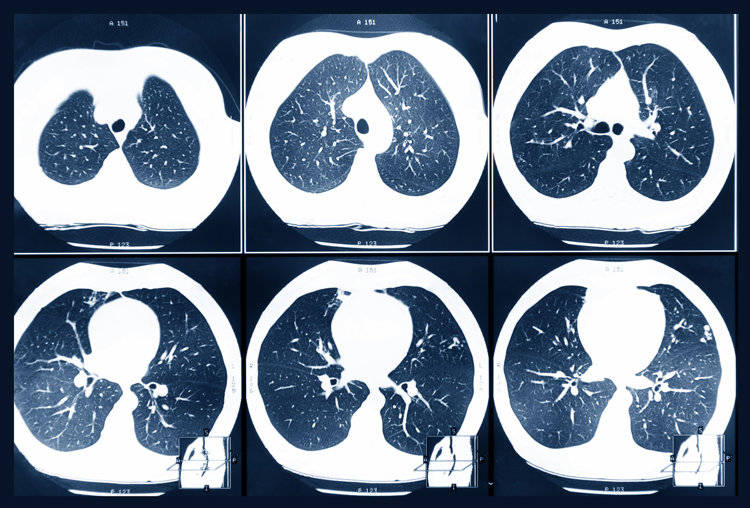

肺癌常见的有肺腺癌和肺鳞癌,无症状的肺癌多见于肺腺癌,一般肺腺癌会发生在支气管、肺泡上皮细胞上,因发生的位置在肺外周,所以也成为周围型肺癌。一些肺腺癌具有惰性生长的特征,尤其是磨玻璃成分的,所以早期症状会更为不明显。

1、持续性增大/直径≥8mm的肺结节

肺结节是现代人身上的常见问题,但如果肺结节持续变大,随访3~6个月发现结节增大≥2mm,一定要高度警惕可能是恶性的。还有就是查出直径≥8mm的肺结节,也可能是恶性的,概率为5~10%。

2、磨玻璃结节/密度

纯磨玻璃结节一般恶性的程度会低一些,如果是混合磨玻璃结节的话,则恶性程度会明显上升。但也要结合结节的大小来进行判断,即便是纯磨玻璃结节,体积≥10mm,恶性程度也很高。

3、分叶状/毛刺征/胸膜凹陷征

分叶状是指结节边缘不光滑,是由于肿瘤向各方向生长不均匀所致。一旦发现结节有明显的分叶,恶性程度会明显增加;

毛刺征则是指结节边缘呈细线状/毛刷状以放射状分布,这是由于肿瘤组织浸润周围组织生长所致,也可能是肿瘤周围的炎性反应导致的纤维化,一般是恶性肿瘤的征兆;

胸膜凹陷征是结节和胸膜之间有明显的三角形、幕状影像,多在肺癌患者身上出现。